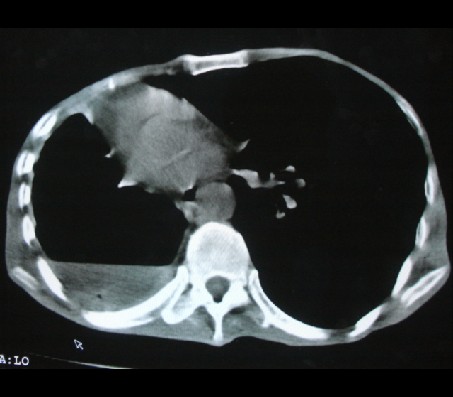

标题: CT17018:肺脓肿?左侧胸腔积液?请会诊! [打印本页]

标题: CT17018:肺脓肿?左侧胸腔积液?请会诊!

男性,65岁,有肺结核病史。

1)两肺继发性肺结核伴右肺毁损,右肺多发空洞及肺大泡形成并感染,伴左肺支气管播散。右侧液气胸.2)右侧胸膜增厚、粘连。3)纵隔疝(左→右)。

液气胸,毁损肺。老结核,纵隔疝。